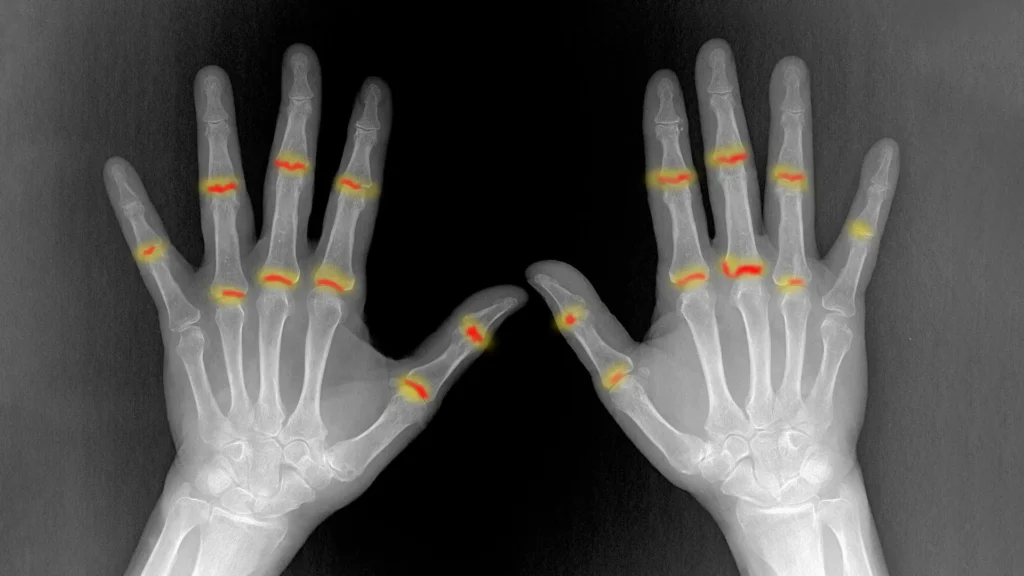

Summarize this content to 100 words: Researchers have figured out how psoriasis can quietly turn into joint disease for some patients. Immune cells formed in inflamed skin can travel through the blood and reach the joints, where they sometimes trigger inflammation. The key difference lies in the joint’s ability to keep those cells in check. This insight could help doctors identify warning signs early and prevent lasting joint damage.